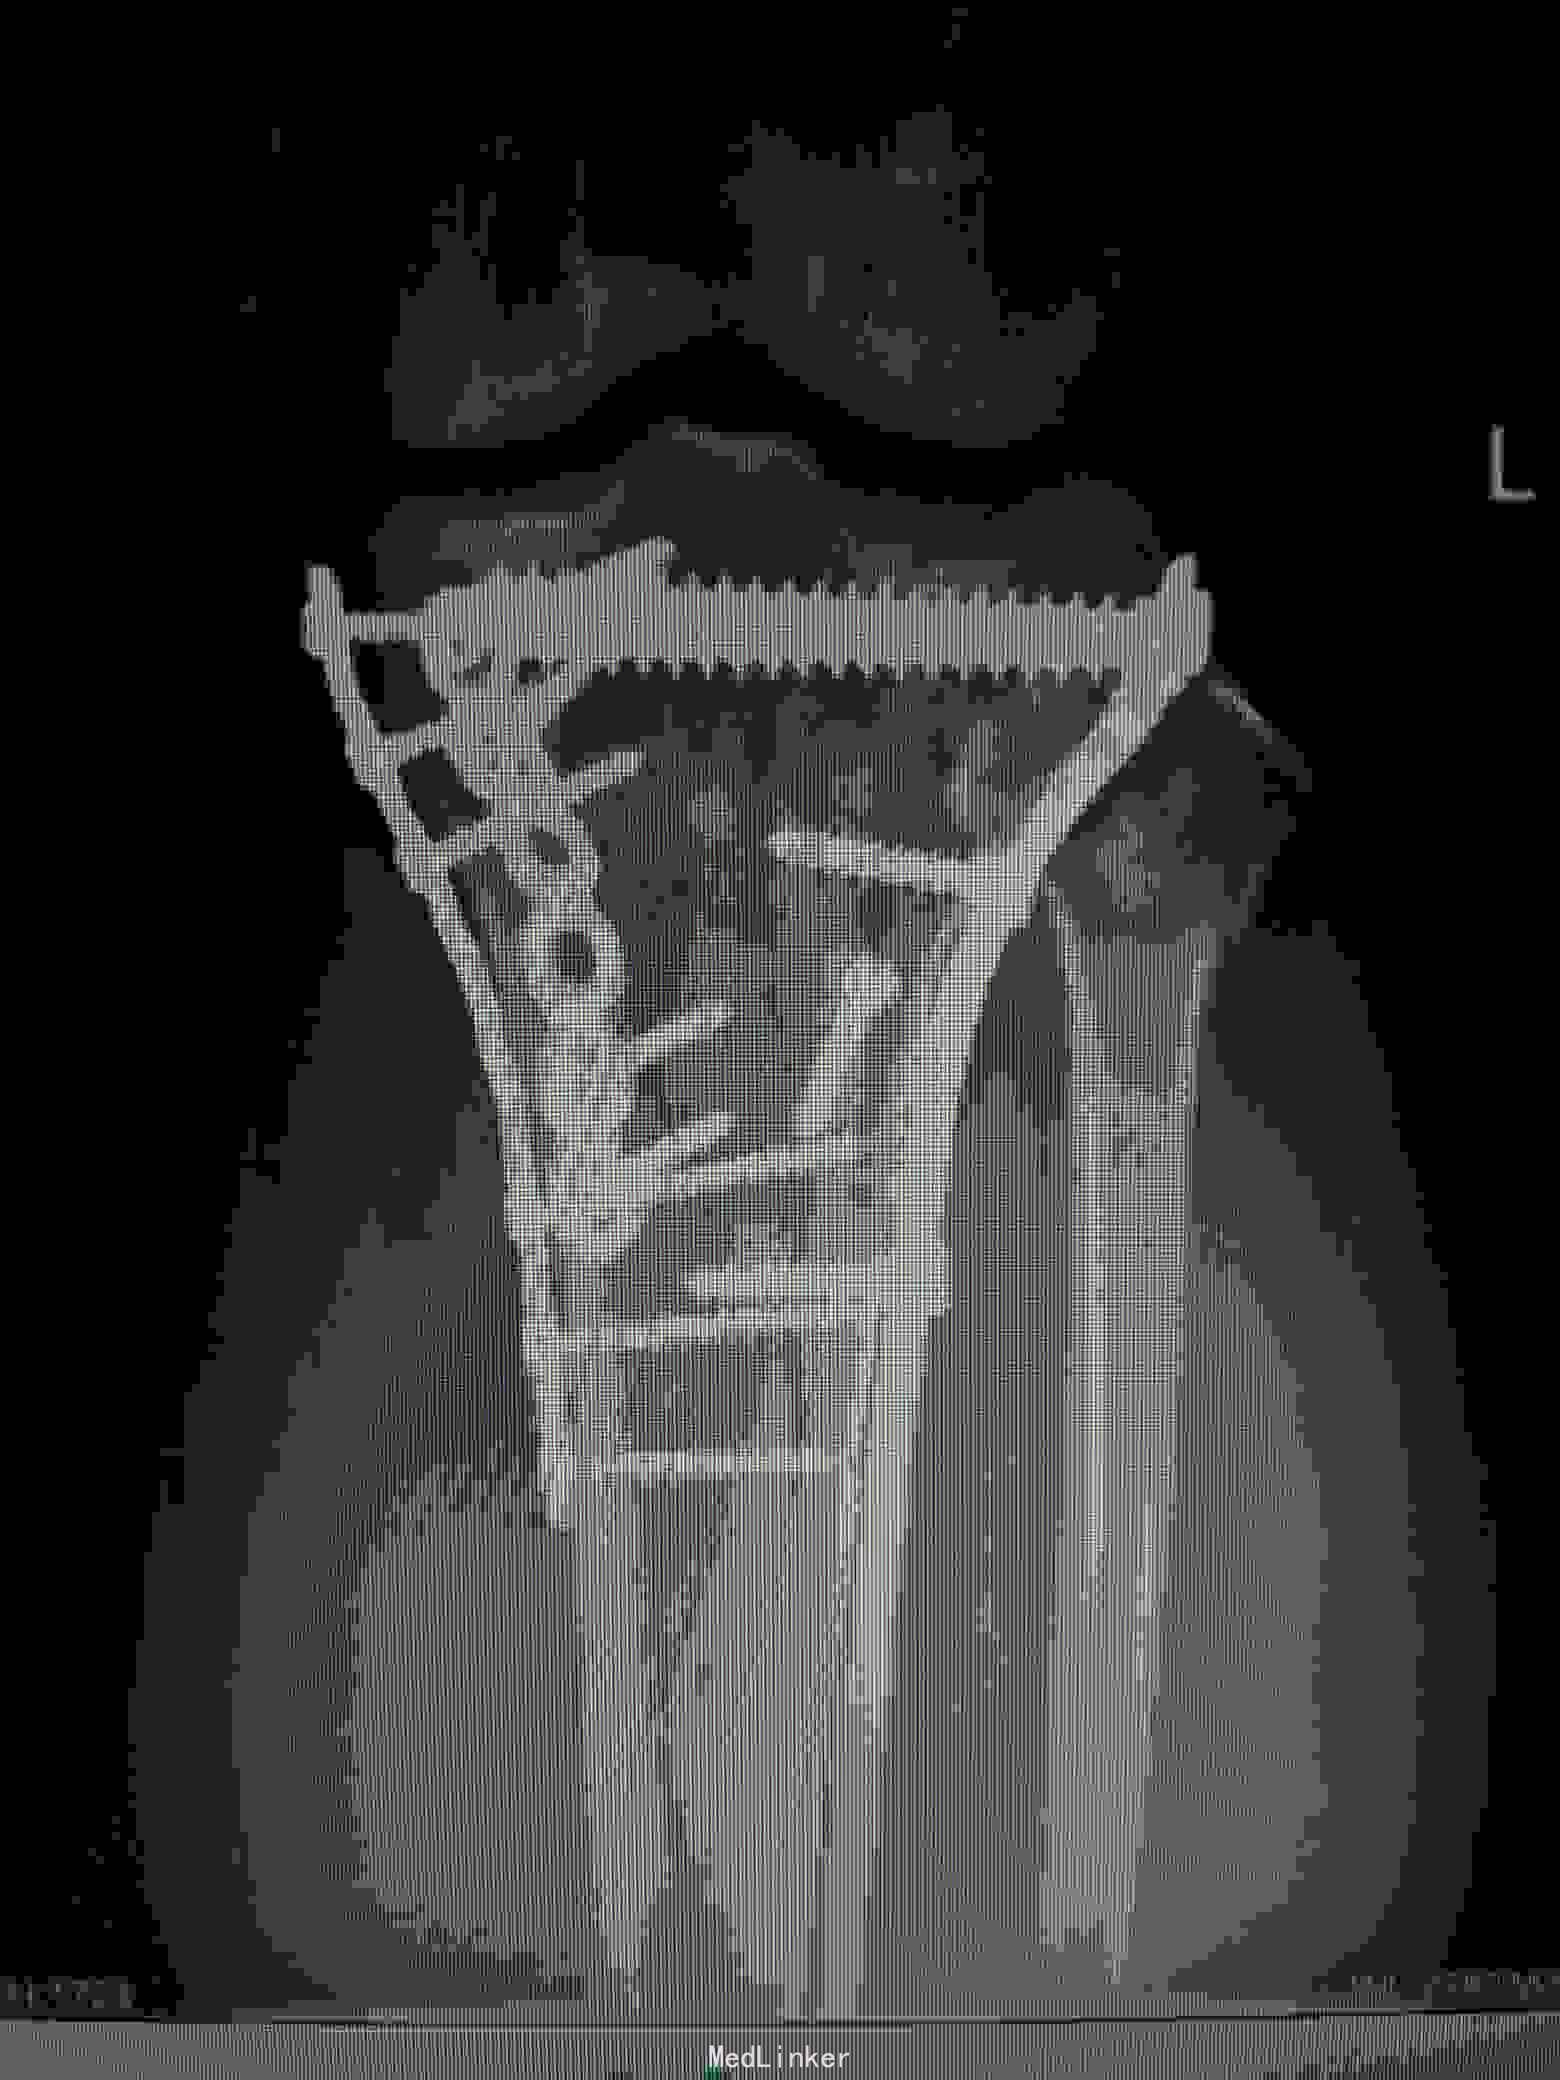

术后复查X线片提示:骨折端对位对线好,力线平。

讨论:内外侧胫骨平台骨折,正常情况下只需在仰卧位下分别行内侧及前外侧入路进行内外侧柱的固定,但是如果骨折累计后内侧骨块,单纯内侧钢板固定仍无法稳定骨折端,这时候需要后内侧钢板的固定,仰卧位下无法清楚显露后内侧骨块,并进行固定,我们采用俯漂体位进行复位固定,俯卧下行后内侧入路,可以清楚显露后内侧及内侧骨块,同时可方便进行固定。

骨折还是碎的挺厉害的,从后侧入路要注意避免损伤重要的血管神经,这个手术基本上胫骨平台一圈都被剥离了,注意术后血供和愈合。